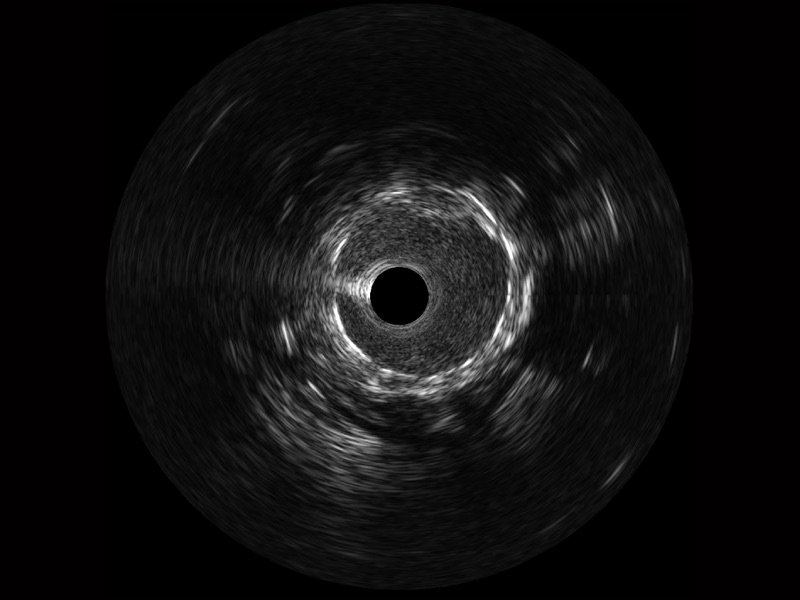

• 传统IVUS图像

对比传统IVUS导管成像,16877太阳集团宽频IVUS图像的近场支架梁显影更细腻,远场中膜外血管仍清晰可辨,兼顾远中近,兼顾分辨力与穿透深度